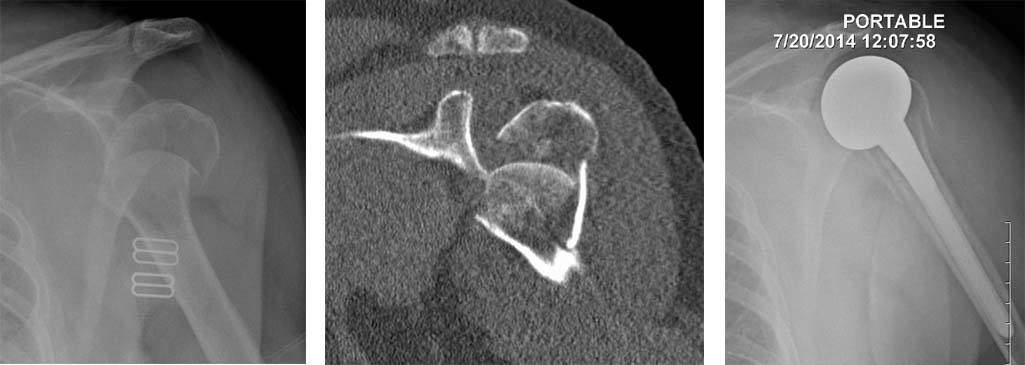

1. A 58 year old male with a fall at home and a severe fracture of the head of the humerus. The middle panel is a 3 dimensional reconstruction of the fracture showing the multiple pieces involved. He was treated with a plate and screws.

2. A 64 year old female with a fall in outdoors with a severe fracture of the head of the humerus. The middle panel shows the head to be disintegrated into multiple small fragments. She was treated with partial shoulder replacement.